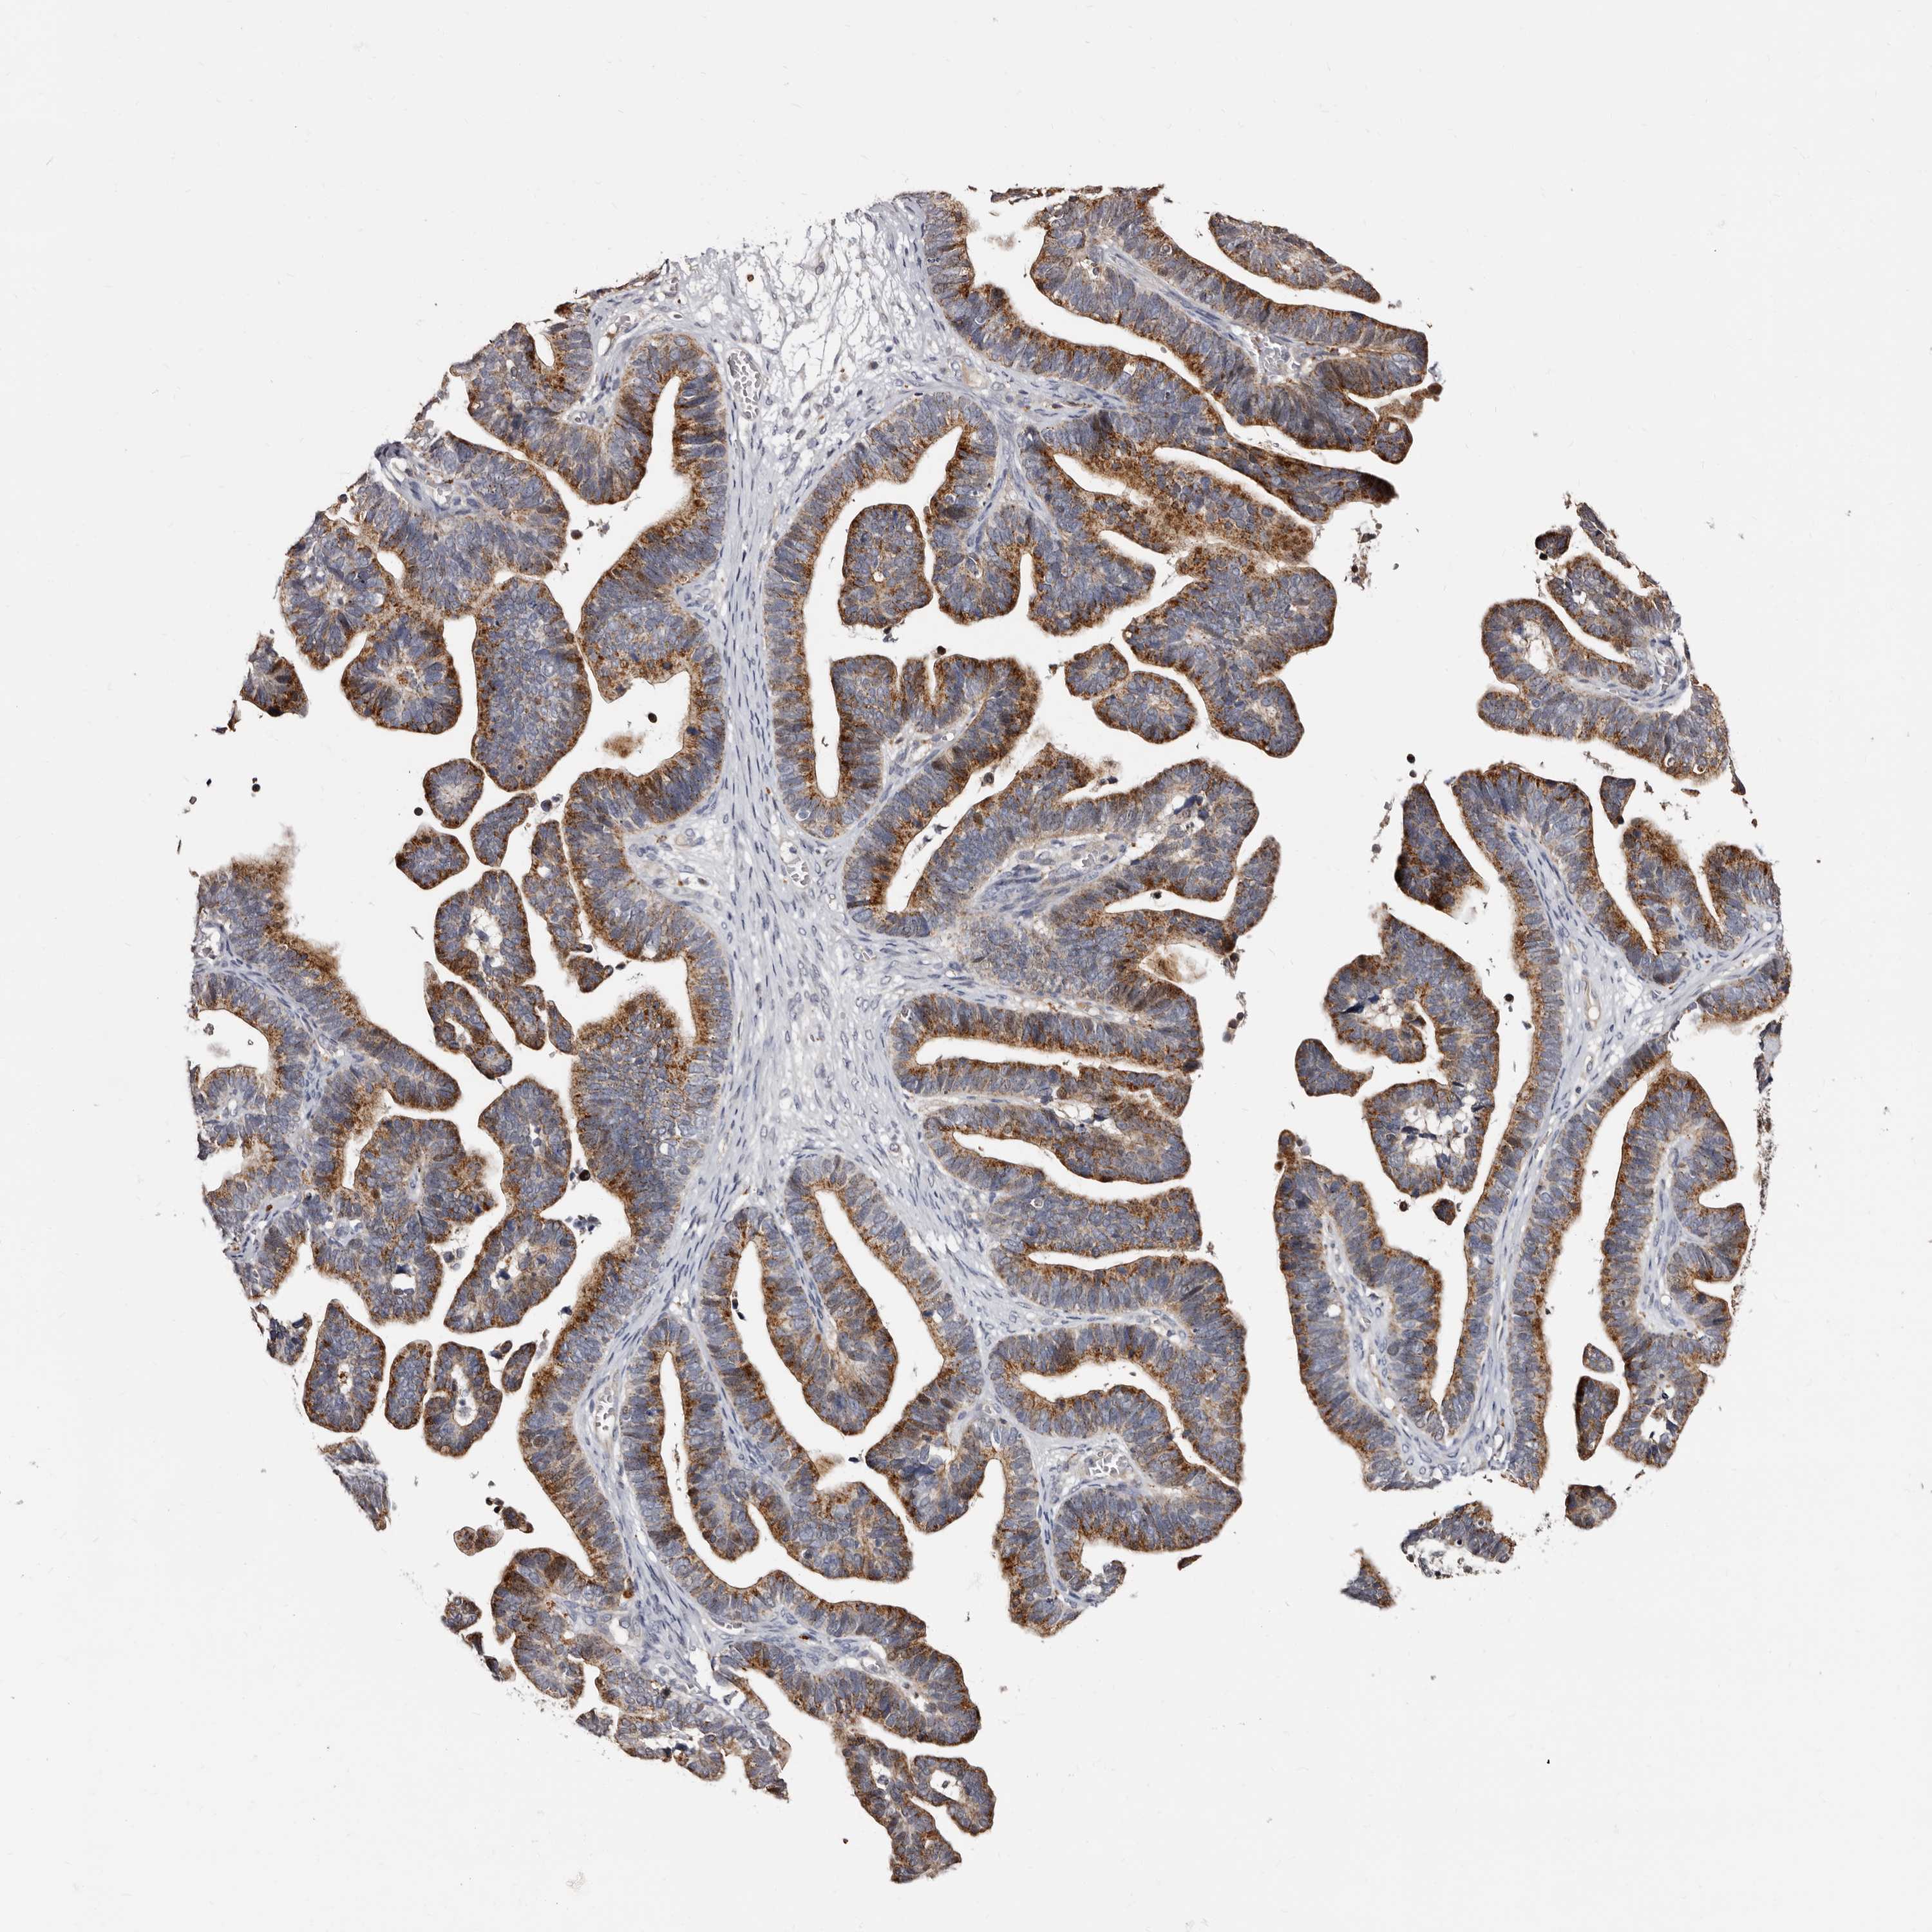

OVARIAN CANCER - Protein expressioni

A mouse-over function shows sample information and annotation data. Click on an image to view it in a full screen mode. Samples can be filtered based on level of antibody staining by selecting one or several of the following categories: high, medium, low and not detected. The assay and annotation is described here.

Note that samples used for immunohistochemistry by the Human Protein Atlas do not correspond to samples in the TCGA dataset.

Antibody stainingi

Antibody staining in the annotated cell types in the current human tissue is reported as not detected, low, medium, or high, based on conventional immunohistochemistry profiling in selected tissues. This score is based on the combination of the staining intensity and fraction of stained cells.

Each image is clickable and will lead to virtual microscopy that enables deeper exploration of all samples and also displays staining intensity scores, fraction scores and subcellular localization as well as patient and tissue information for each sample.

Antibody HPA027543

Staining

High

Medium

Low

Not detected

Intensity

Strong

Moderate

Weak

Negative

Quantity

>75%

75%-25%

<25%

None

Location

Nuclear

Cytoplasmic/membranous

Cytoplasmic/membranous,nuclear

Cystadenocarcinoma, serous, NOS

Carcinoma, endometroid

Cystadenocarcinoma, mucinous, NOS

Carcinoma, NOS